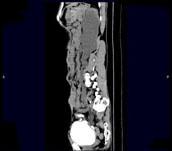

问题 男,55岁,尿频,尿痛伴低热乏力1个月。如图所示,下列说法正确的是 ( )

选项 A、左侧输尿管结核 B、左侧输尿管癌 C、右侧肾积水 D、膀胱变形 E、左侧输尿管多发性狭窄

答案 ACDE